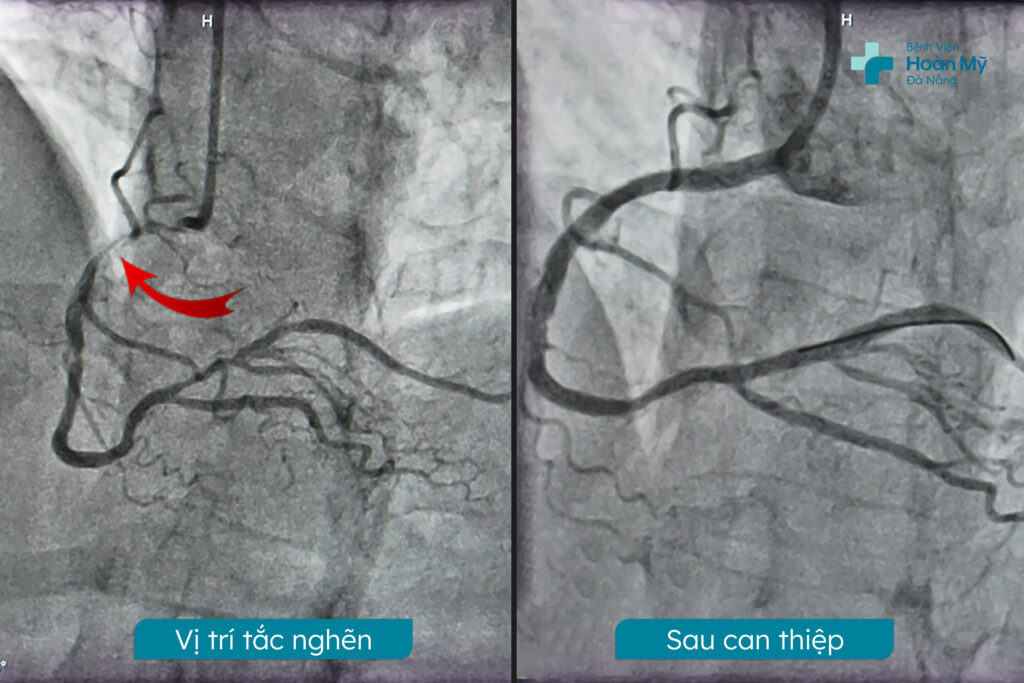

Kết quả chụp mạch vành qua da: tổn thương 3 nhánh mạch vành: hẹp nặng động mạch vành phải dòng chảy chậm, mạch mủ hẹp nặng nhiều vị trí cả lỗ vào, hẹp trung bình đoạn đầu liên thất trước từ ngay lỗ vào. Theo ý kiến chuyên khoa, trường hợp này sẽ có hai phương pháp điều trị: phẫu thuật mổ bắt cầu hoặc can thiệp nội mạch. Mỗi phương pháp đều có ưu điểm và rủi ro riêng. Sau khi được bác sĩ tư vấn kỹ lưỡng về cả hai phương pháp, gia đình người bệnh đã quyết định lựa chọn can thiệp nội mạch – không phải mở ngực hở và giúp phục hồi nhanh hơn.

Bác sĩ đã tiến hành can thiệp động mạch vành phải bằng cách đặt hai stent phủ thuốc nhằm tái thông dòng chảy máu về trạng thái bình thường. Cơ thể bệnh nhân phản ứng tích cực với can thiệp, cho thấy tín hiệu khả quan. Sau thủ thuật, tình trạng sức khỏe của người bệnh đã được cải thiện rõ rệt và duy trì ổn định.

Kết quả thủ thuật thành công như mong đợi. Các tổn thương đoạn xa của động mạch mũ và đoạn I LAD được mở rộng lòng mạch bằng stent phủ thuốc. Vị trí chổ chia thân chung lựa chọn chiến lược kỹ thuật Mini Crush với 2 Stent phủ thuốc loại tốt. Các stent được đặt chính xác vào các vị trí tổn thương, giúp mở rộng lòng mạch và cải thiện lưu lượng máu đến tim.